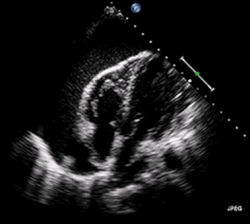

A 2D echo transthoracic echocardiogram of pericardial effusion. The "swinging" heart.

ECG: may present with sinus tachycardia, low voltage QRS as well as electrical alternans.[2] Due to the fluid accumulation around the heart, the heart is further away from the chest leads, which leads to the low voltage QRS. Electrical alternans signifies the up-and-down change of the QRS amplitude with every beat due to the heart swinging in the fluid (as displayed in the ultrasound image in the introduction) .[1] These three findings together should raise suspicion for impending hemodynamic instability associated with cardiac tamponade.

Echocardiogram (ultrasound): when pericardial effusion is suspected, echocardiography usually confirms the diagnosis and allows assessment of the size, location and signs of hemodynamic instability.[4] A transthoracic echocardiogram (TTE) is usually sufficient to evaluate pericardial effusion and it may also help distinguish pericardial effusion from pleural effusion and MI. Most pericardial effusions appear as an anechoic area (black or without an echo) between the visceral and the parietal membrane.[1] Complex or malignant effusions are more heterogeneous in appearance, meaning they may have variations in echo on ultrasound.[5] TTE can also differentiate pericardial effusion based on the size. Although it's difficult to define size classifications because they vary with institutions, most commonly they are as follows: small <10, moderate 10–20, large >20.[5] An echocardiogram is urgently needed for evaluation when there is concern for hemodynamic compromise, a rapidly developing effusion or history of recent cardiac surgery/procedures.[1]